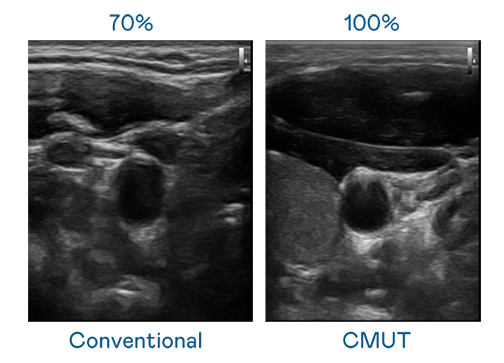

CMUT 技術是一種用電容式微機電元件來產生超音波訊號的技術。與傳統 PZT 壓電式技術相比,CMUT 頻寬增加 30%,更寬頻的超音波訊號讓影像解析度大幅提升,是實現高影像品質醫療超音波掃描、促進精準醫療發展的關鍵技術。

超音波影像的解析度高低,首先取決於探頭能發出的訊號頻寬。球速体育 CMUT 可提供高清晰的超音波訊號,提供高頻寬、高靈敏度、影像紋理細節更高的超音波影像,協助醫護人員縮短影像判讀時間及利用精準的醫療影像進行診斷。